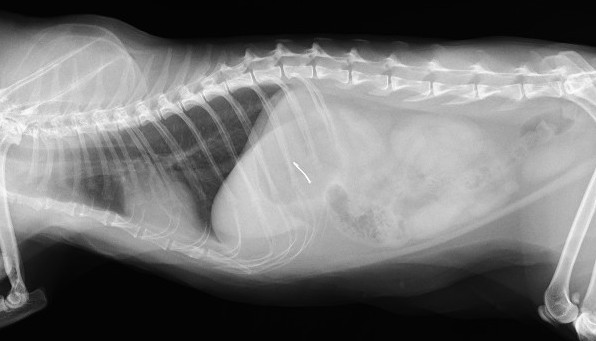

腸内の紐状異物は、動物が誤って糸や紐、ビニールテープなどを誤飲した場合に、腸に引っかかってアコーディオン状に手繰り寄せられる非常に危険な状態です

重度の腸閉塞や腸管が裂け腹膜炎などを引き起こし、通常緊急手術が必要となります

レントゲンにて胃内にX線不透過物(釣り針)、腹部エコーにてアコーディオン状に手繰り寄せられた消化管と紐状異物を確認

釣り針の誤食ならびに糸による紐状異物と診断